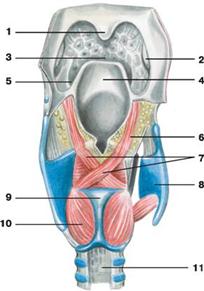

Рис. Мышцы гортани (вид сзади):

Рис. Мышцы гортани (вид сзади):

1 — язычок; 2 — небная миндалина;

3 — корень языка; 4 — надгортанный хрящ;

5 — боковая складка слизистой оболочки; 6 — черпалонадгортанная мышца;

7 — поперечная черпаловидная мышца; 8 — щитовидный хрящ;

9 — перстневидный хрящ; 10 — задняя перстнечерпаловидная мышца;

11 — перепончатая стенка трахеи

Мышцы гортани начинаются от одних и прикрепляются к другим ее хрящам. По функции они делятся на 3 группы: расширители голосовой щели, суживатели и мышцы, натягивающие (напрягающие) голосовые связки.